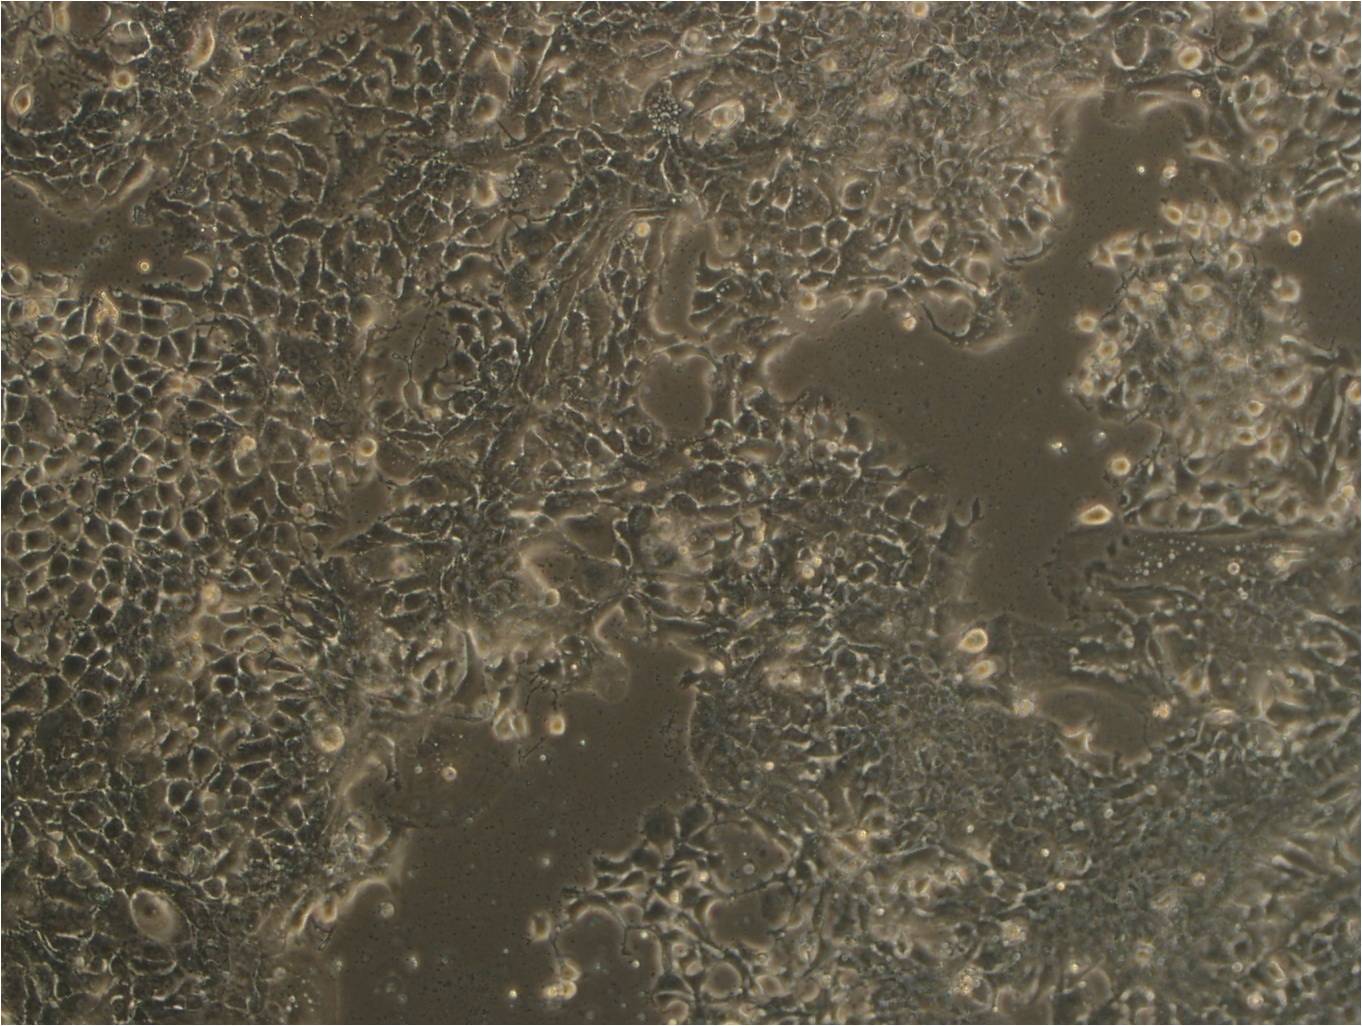

MDA-MB-415 人乳腺腺癌细胞

特征特性 该细胞源于一名38岁患有乳腺腺癌女性的胸腔积液,细胞表达WNT7B癌基因。带瘤患者来自巴拉圭,虽然填报的是白人,但细胞表型存在G6PD A型,显示其属于混血。细胞株形成平展延伸的上皮细胞样,在电镜下呈现结节,伴随着延伸的微管和微板。不容易用胰酶消化。

形态特征 上皮细胞样

生长特征 贴壁